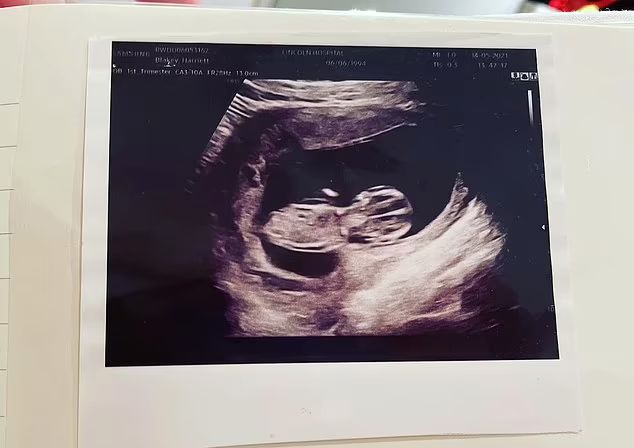

Niestety zaledwie kilka dni później, kiedy Harriett poszła na kolejne badanie ultrasonograficzne, okazało się, że są problemy ze znalezieniem płodu. Nie był aktywny jak poprzednio, a lekarka poprosiła bardziej doświadczoną koleżankę, by wytłumaczyła młodej mamie, co się dzieje.

Kobieta wyjaśniła Harriett, że widoczna jest znacznie podwyższona przezierność karkowa (odległość między tkanką podskórną a skórą, na wysokości karku płodu). Oznacza to, że ryzyko wystąpienia nieprawidłowości chromosomowej, wad serca i innych chorób uwarunkowanych genetycznie jest bardzo wysokie.

USG Harriett

USG Harriett © Facebook

- Pokazała mi USG i wskazała na czarny obszar na karku dziecka. Wytłumaczyła mi, że tego płynu nie powinno tam być i jest to poważny problem – mówi Harriett. - Rozmawiano ze mną tak, jakby moje dziecko już umarło. Nie mogłam w to uwierzyć – dodaje.